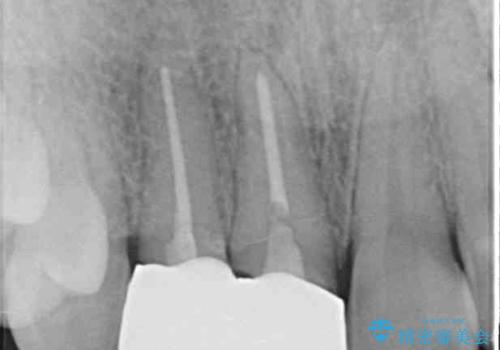

クラウンの状態は、根管治療の状態も含めて決して良い状態とは言えず、矯正治療後の根管治療と補綴治療の再治療を前提として、インビザラインによる矯正治療を行うこととしました。

矯正治療中に前歯2本のクラウンは外れてしまい、途中仮歯に替える必要があったので期間は掛かりましたが、歯列も整い、負担のかからない咬み合わせを達成することができました。